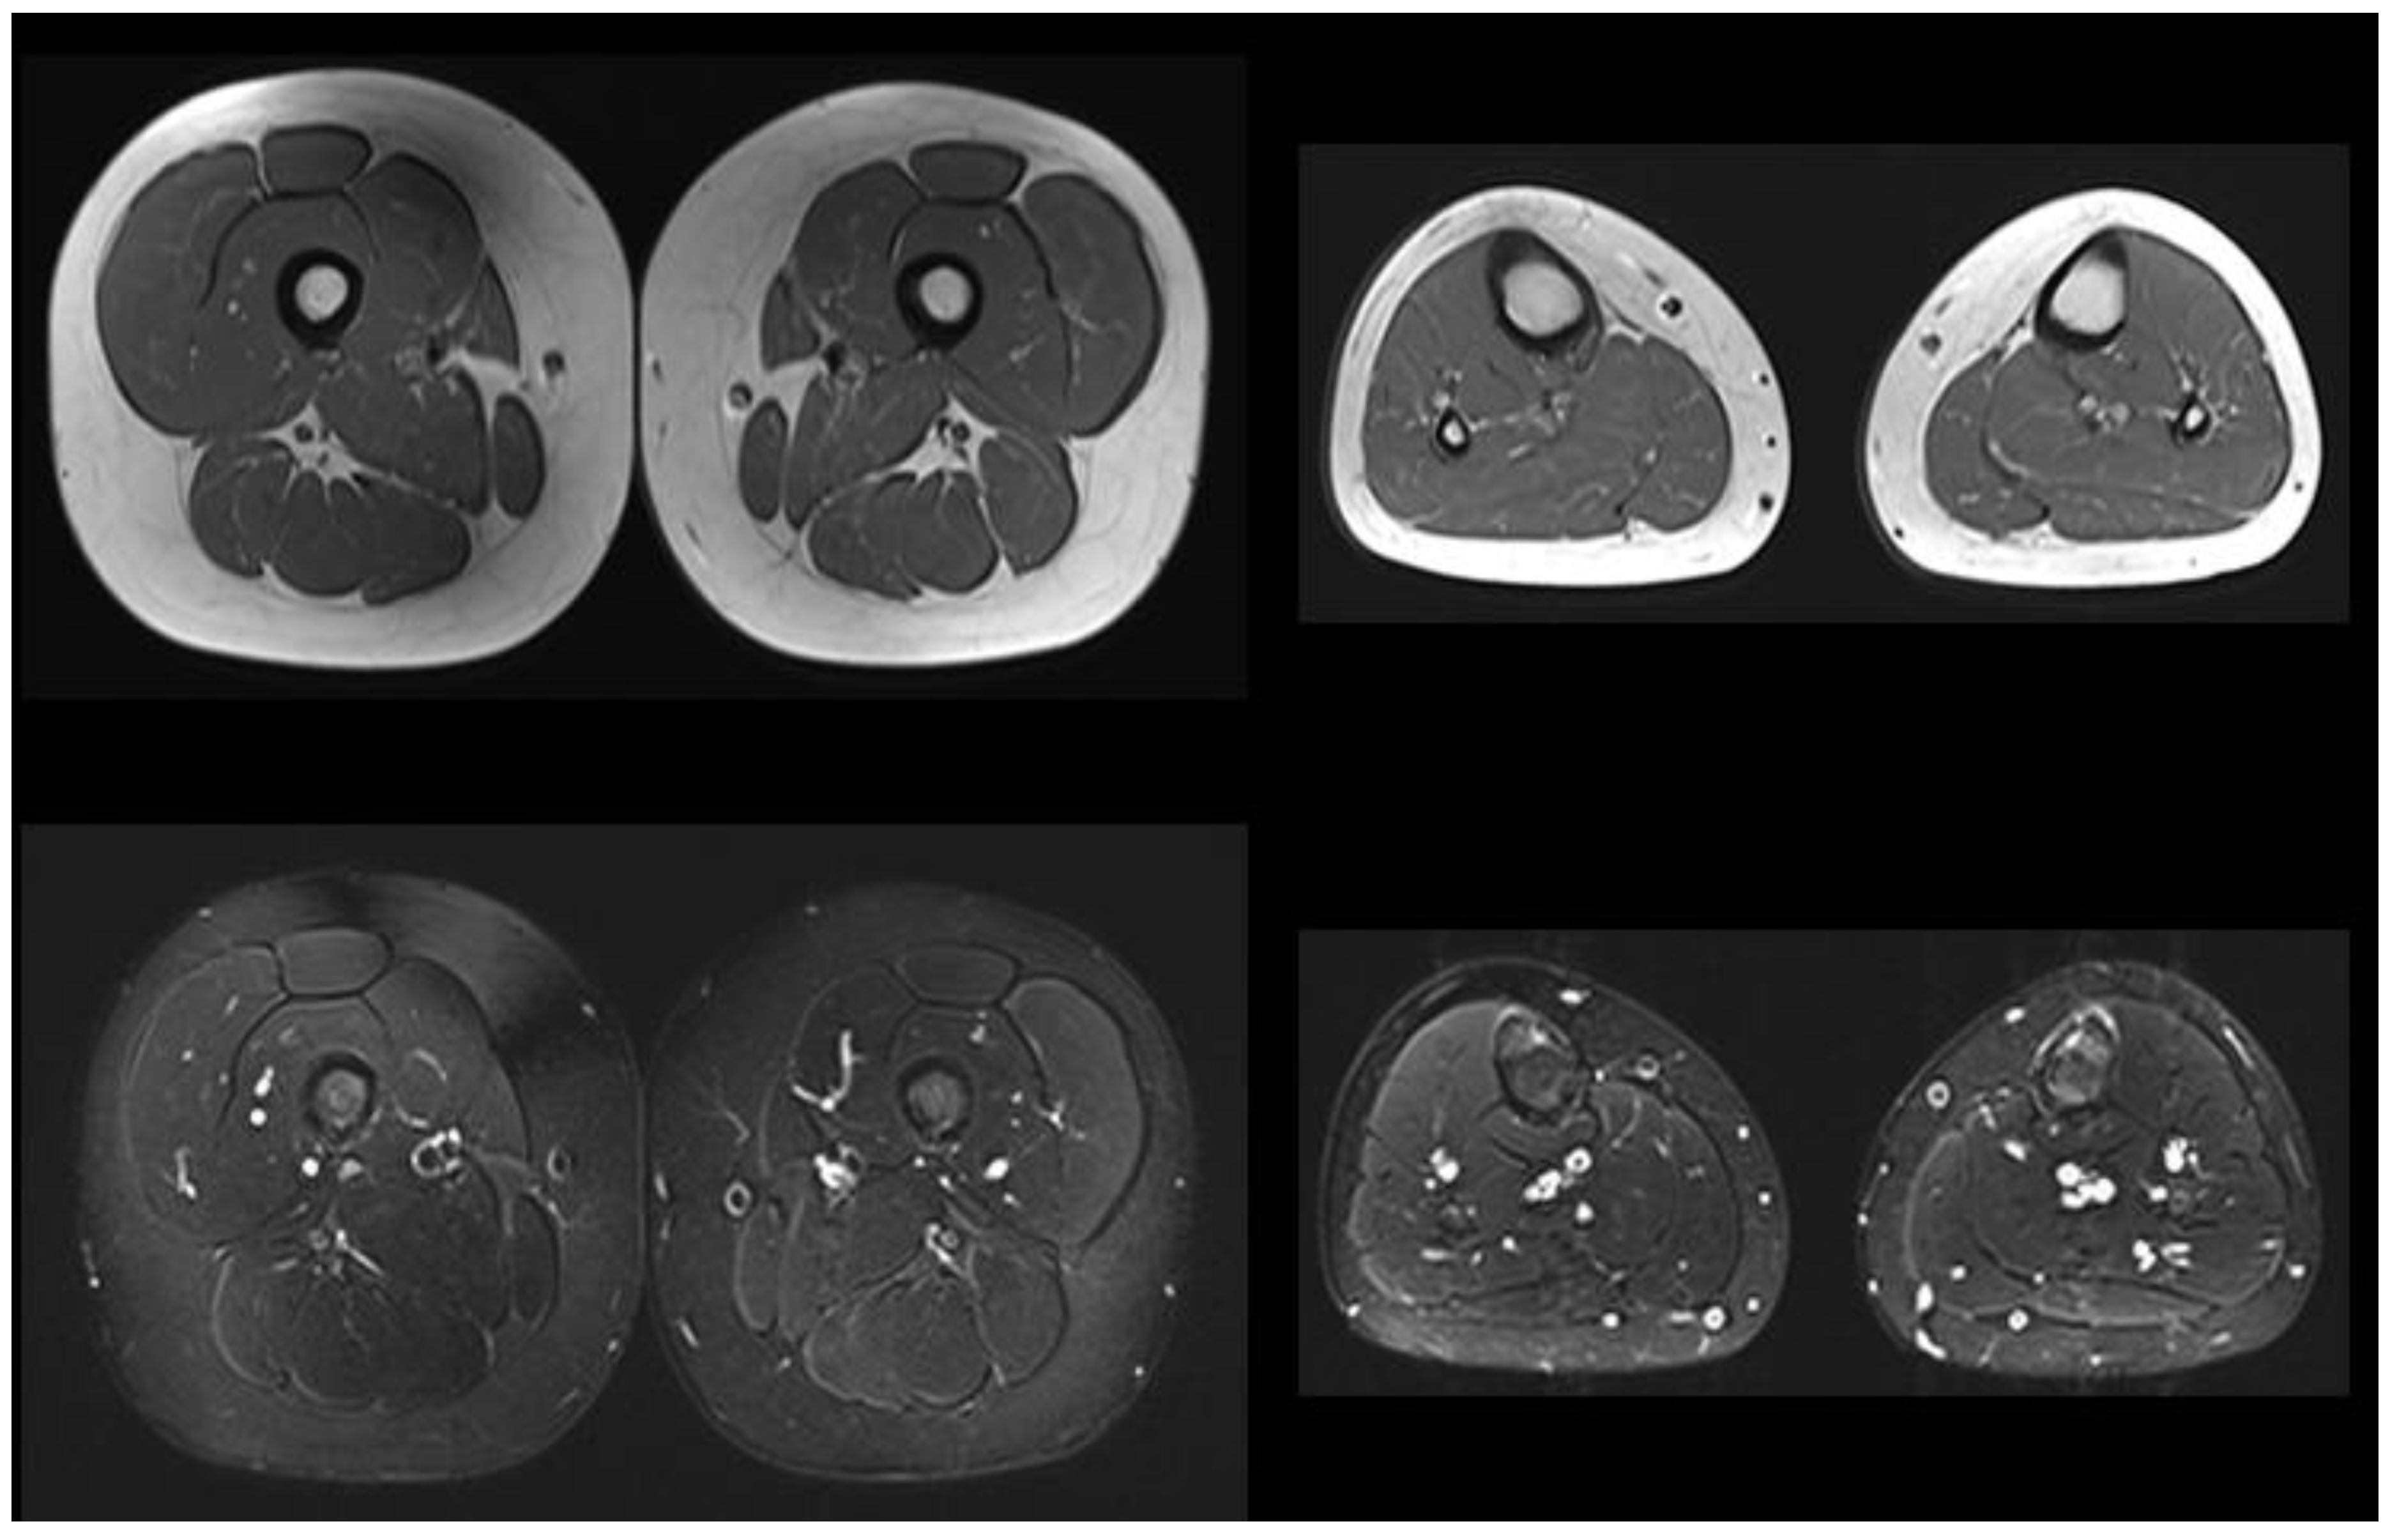

The older brother (patient 3) underwent screening for Pompe disease when he was 10 years old. His history was negative. Echocardiography and neurologic assessment results were normal; enzyme activity on the dry blood spot result was borderline (1.2 µmol/L/h, n.v. > 2); and GAA sequencing revealed the same mutations as the younger siblings. An abdomen ultrasound, electromyography, and muscle MRI were all normal (Figure 2), with no signs of selective fat replacement or edema on STIR. He was also referred to our center. He played sports three times a week and reported no symptoms. He did not present any signs of myopathy. Blood tests (CPK 183U/L, AST 20U/L, LDH 252U/L, pro-BNP 52pg/mL, and CK-MB 3.3ng/mL), urinary tetrasaccharide (0.69 mmol/mol Cr, n.v. 0.08–1.37), 6MWT, and spirometry were all normal.

Figure 2. Lower limb muscles MRI of the older brother when 10 years old; T1-weighted (top) and STIR images (bottom) are shown. No significant fat replacement or edema changes are detected at the thigh and leg levels, bilaterally.